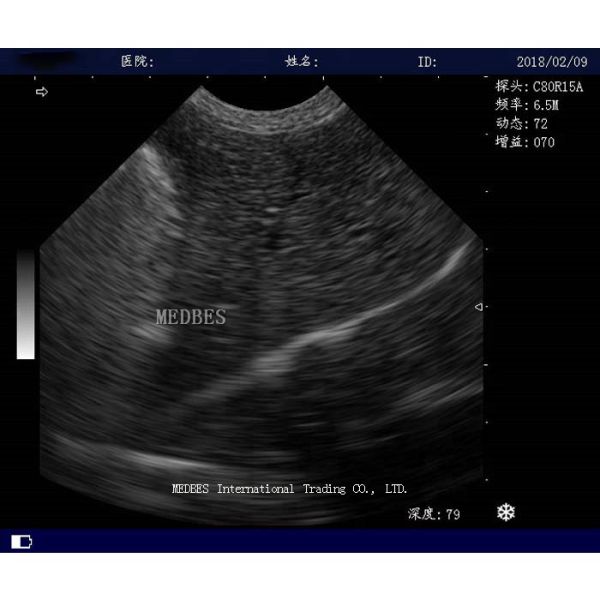

Full-digital Trolley Ultrasound Scanner

First-class digital imaging technology, more clearer image:

Full-digital beam imaging technology

Real-time dynamic receiving focus point by point

Real-time dynamic sound velocity changed

High-accuracy DSC Digital image formation technology

Intelligentized 8-segment TGC adjustment

2D Trolley Black and White Ultrasoudn Scanner with convex probe Images |